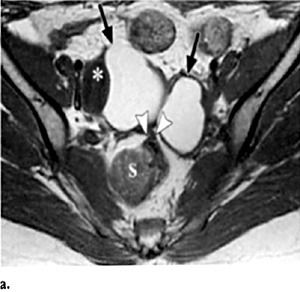

Εικόνα 2. Ωοθηκικά ενδομητριώματα. Εγκάρσιες Τ1(Α) και Τ2(Β) εικόνες μαγνητικής τομογραφίας αμφοτερόπλευρων ωοθηκικών ενδομητριωμάτων. Υψηλής έντασης σήμα και στις δύο ακολουθίες (βέλη), χαρακτηριστικό των ενδομητριωμάτων. Χαμηλής έντασης σήμα μεταξύ των ωοθηκών (κεφαλή βέλους) και του σιγμοειδούς (S), που αντιστοιχεί σε ινώδεις συμφύσεις. *=ωοθυλάκιο

H μαγνητική τομογραφία (MRI) έχει αποδειχθεί ως ένα χρήσιμο μη επεμβατικό διαγνωστικό μέσο της ενδομητρίωσης. H μαγνητική τομογραφία υπερέχει της υπερηχογραφίας στην ενδομητρίωση του περιτοναίου, η οποία εμφανίζεται ως πολλαπλά μικρά οζίδια, γιατί μπορεί να ανιχνεύσει την ύπαρξη ενδομητριωσικών εμφυτεύσεων στις Τ1 ακολουθίες με ευαισθησία 11-27% και με σήμα το οποίο ποικίλει σε ένταση ανάλογα με την ενεργό δραστηριότητα και τη χρονική διάρκεια της βλάβης. Στις Τ2 ακολουθίες οι εμφυτεύσεις εμφανίζονται ως μάζες χαμηλού σήματος λόγω της αντιδραστικής ίνωσης που περιβάλλει τις μικρές συλλογές ενδομητριωσικού υλικού, αν και κάποιες φορές στο εσωτερικό των εμφυτεύσεων μπορεί να υπάρχει υψηλής έντασης σήμα λόγω της κυκλικής αιμορραγίας (εικόνα 2). Όταν όμως οι λήψεις της μαγνητικής τομογραφίας λαμβάνονται με καταστολή του λίπους, βελτιώνεται η ανίχνευση των ενδομητριωσικών εμφυτεύσεων στο περιτόναιο, αυξάνοντας την ευαισθησία της μεθόδου στο 47-61% και την ειδικότητα στο 87-97%.